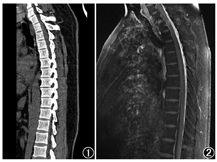

患者男,36岁,无明显诱因突发间断性头晕、头痛3个月余,表现为视物旋转,反复发作,多于活动时出现,每次持续数分钟,严重时伴恶心、呕吐,休息后可好转。否认高血压、冠状动脉粥样硬化性心脏病、糖尿病及外伤史。体格检查:四肢肌张力正常,双侧腱反射对称,未见明显感觉障碍。实验室检查(括号内为正常参考值范围):血常规WBC计数[18.59(3.50~9.50)×109/L]及中性粒细胞百分比稍增高[80%(50%~70%)];丙氨酸氨基转移酶升高[96.0(0.0~50.0) U/L]。颅脑MRI及弥散加权成像(diffusion weight imaging, DWI)未见明显异常。腰椎穿刺后测得脑脊液压力为0.58(0.78~1.76)kPa,脑脊液常规检查结果示细胞总数为1 003.0(0.0~8.0)×106/L,WBC计数为3.0(0.0~5.0)×106/L,蛋白质为0.9(0.2~0.4) g/L。结合病史及上述检查结果,倾向于诊断颅内感染。按照病毒性脑炎治疗后,患者仍间断头痛且剧烈,坐起时明显,最终临床考虑自发性低颅压综合征(spontaneous intracranial hypotension syndrome, SIHS)可能性大,对患者行CT及MRI查找脑脊液漏口。胸部CT(图1)示椎管内未见明显异常,胸、腰椎增强MRI(图2)示椎管内异常强化影,未见明确漏点,首先考虑SIHS。由于上述检查未能发现明确漏点,遂行核素脑池显像,检查前患者签署知情同意书。仪器为美国GE Discovery-670Pro SPECT/CT仪,显像剂99Tcm-二乙撑三胺五乙酸(diethylene triamine pentoacetic acid, DTPA)注射液由本科室自制(注射用亚锡喷替酸由北京师宏药物研制中心提供)。腰椎穿刺成功后,接上装有显像剂的注射器,取缓慢流出的脑脊液稀释至2.5 ml,再缓慢将110 MBq(0.8 ml)显像剂推注到蛛网膜下腔,然后放入针芯,拔针,盖敷料,患者去枕平卧休息30 min。于注入显像剂后0.5、1.5、2及3 h行局部(颈胸段)平面显像,3.5 h行局部SPECT/CT显像。0.5 h平面显像示从腰段至枕大池,脊髓蛛网膜下腔显影,放射性分布均匀,未见明显异常放射性分布浓聚影(图3A);1.5 h及2 h显像示上后纵隔、左侧椎旁见局灶性放射性浓聚影,似与椎管相连(图3B,图3C);3 h显像示上后纵隔、左侧椎旁放射性影像较前稍增浓(图3D);3.5 h SPECT/CT显像示胸2椎水平左侧附件区、椎管旁见局限性放射性浓聚影且与椎管影像相连(图4)。根据核素脑池显像影像表现,临床行手术探查,术中在显微镜下可见胸2神经根处蛛网膜撕裂并漏出清亮脑脊液,仔细分离出漏口,2次缝扎并用耳脑胶封闭漏口处。术后1个月及1年随访2次,患者已无头痛、头晕等症状,临床治愈。